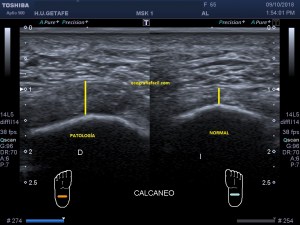

Es muy útil para lesiones que han crecido mucho y no podemos conjugar en una sola imagen, por ejemplo, un lipoma, cuando superan la medida de la huella de la sonda no son medibles, hay que usar «panoramic view», y como este caso, otros muchos.

En la imagen 3 ves una imagen de un lipoma, mide 7 cms, la huella de la sonda mide 5cms, la «panoramic view» posee una regla centimetrada que sigue el contorno de la imagen, justo en la profundidad de la misma y lo marca la flecha amarilla. La profundidad la marca la flecha roja y la flecha blanca marca el rango centimetral de los 5cms, fíjate que la línea blanca es ligeramente mayor cada 5 cms. Sirve de referencia, como en la imagen 4 donde ves una colección en el glúteo de más de 10 cms.